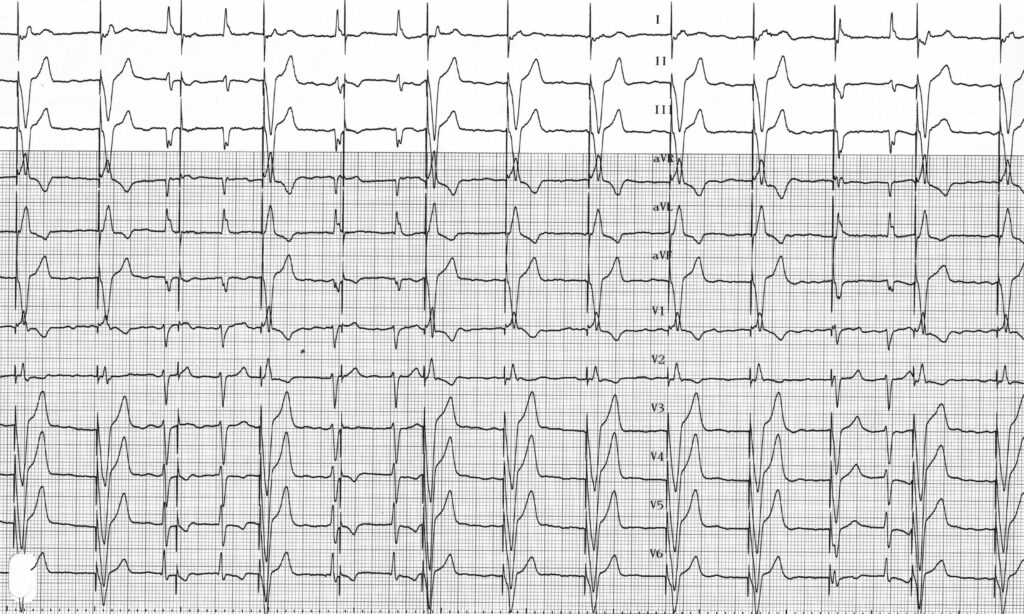

Tracé 4.8: Défauts de détection ventriculaire

Homme implanté d’un stimulateur fonctionnant en mode VVI dans le cadre d’une maladie de l’oreillette (alternance entre dysfonction sinusale et épisodes de fibrillation auriculai­ re); électrocardiogramme de contrôle

L’électrocardiogramme montre une fibrillation auriculaire; les QRS spontanés ne sont pas détectés et n’inhibent pas la stimulation ventriculaire qui est efficace; défauts de détection ventriculaire;

Ce tracé révèle une sous-détection ventriculaire entrainant parfois une stimulation en période vulnérable. En l’absence de détection correcte, le stimulateur fonctionne en mode asynchrone avec impossibilité d’inhibition sur les ventricules spontanés. Il existe un risque théorique faible mais non nul d’induction d’une arythmie ventriculaire polymorphe maligne compromettant la survie du patient. De plus cette stimulation inutile entraine une consommation d’énergie préjudiciable pour la durée de vie de l’appareil.

Une sous-détection atriale ou ventriculaire se traduit sur l’électrocardiogramme par l’existence d’artéfacts de stimulation à fréquence fixe en dépit de l’existence de complexes spontanés qui n’inhibent pas la stimulation.